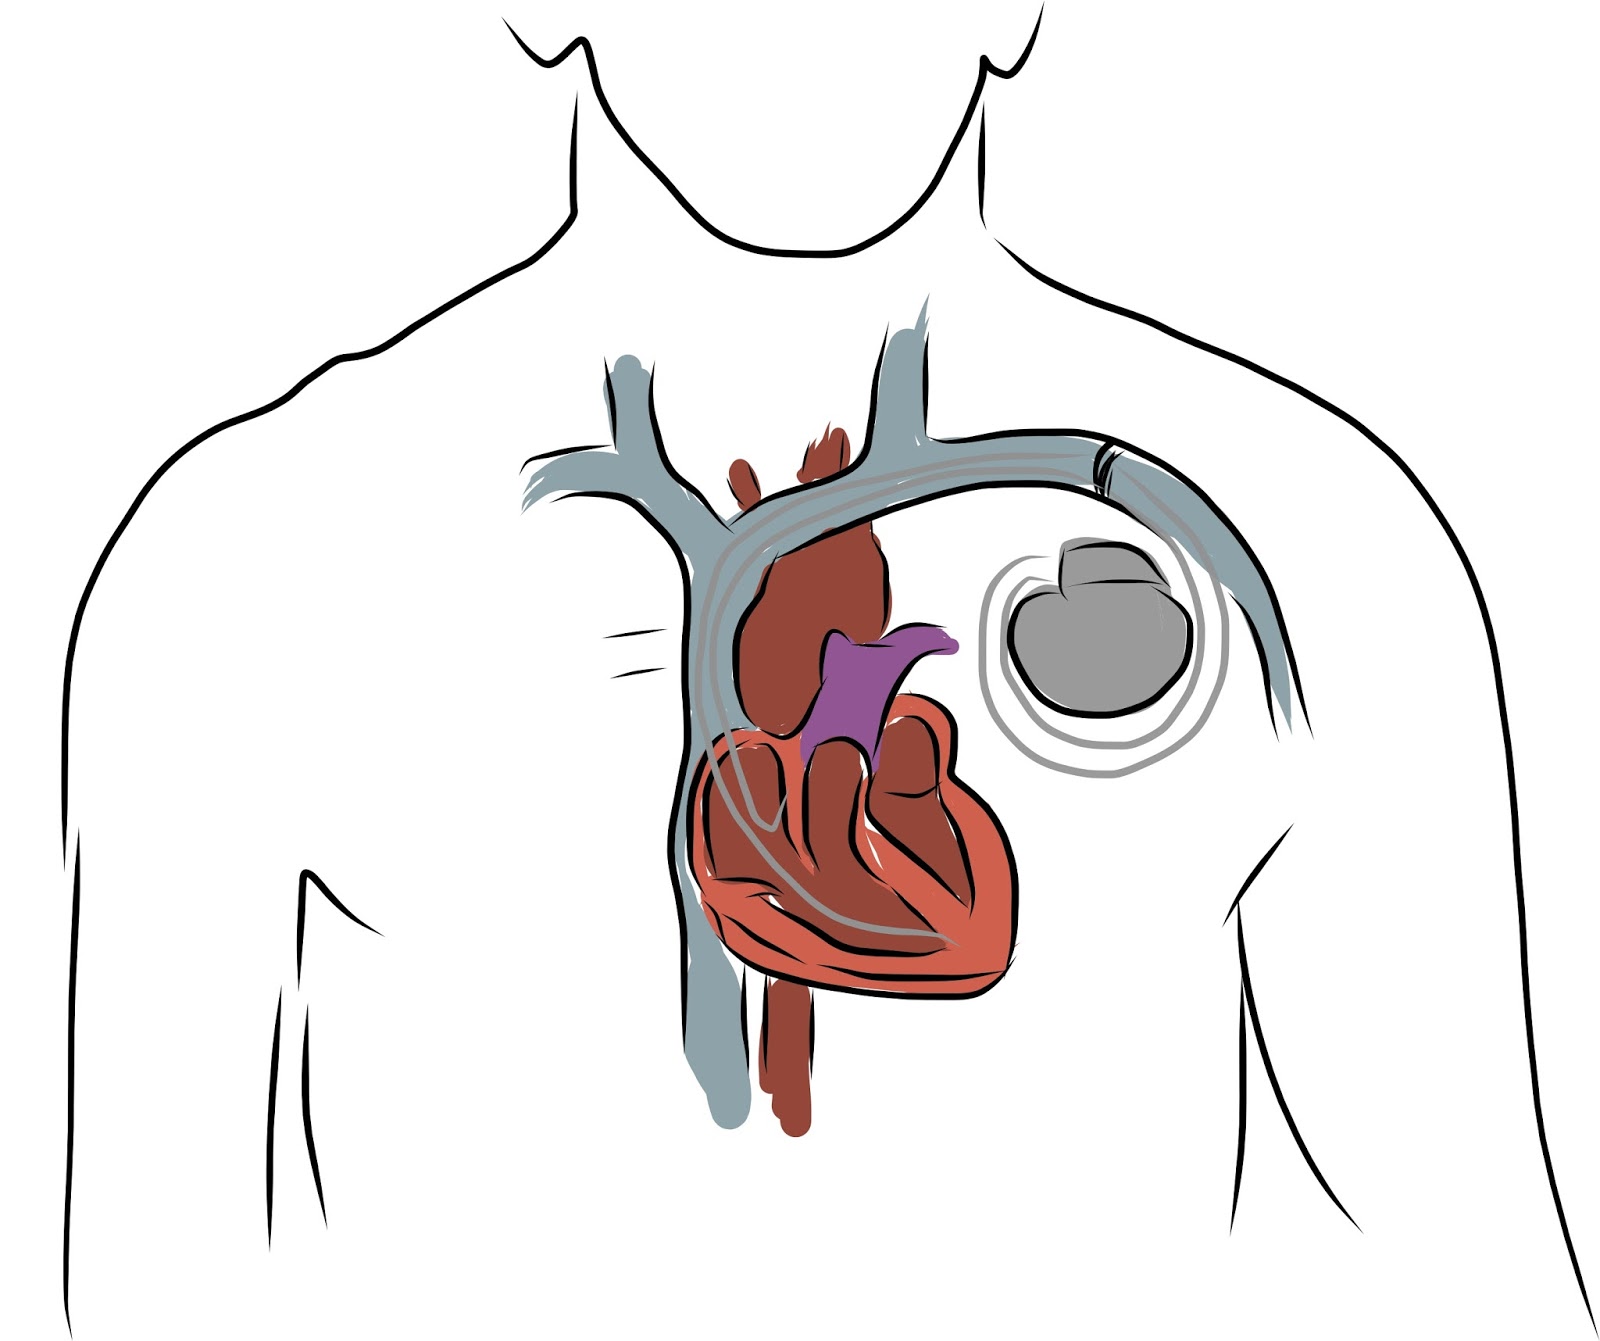

Nei giorni scorsi a Pisa è stato effettuato con successo il primo impianto del più piccolo pacemaker senza fili al mondo. L’impianto rientra nello studio clinico mondiale Micra ed è stato effettuato, per la prima volta in Italia, da Maria Grazia Bongiorni, direttore dell’Unità operativa di Cardiologia 2 dell’Aoup-Azienda ospedaliero-universitaria pisana, coadiuvata dalla sua équipe. L’assessore al diritto alla salute della Regione Toscana, Luigi Marroni, ha espresso grande soddisfazione per questo impianto e si è congratulato con la dottoressa Bongiorni e con l’intera équipe che ha eseguito l’intervento, sottolineando che l’azienda ospedaliero-universitaria pisana è uno dei pochi centri al mondo che partecipano a questo studio.

Nei giorni scorsi a Pisa è stato effettuato con successo il primo impianto del più piccolo pacemaker senza fili al mondo. L’impianto rientra nello studio clinico mondiale Micra ed è stato effettuato, per la prima volta in Italia, da Maria Grazia Bongiorni, direttore dell’Unità operativa di Cardiologia 2 dell’Aoup-Azienda ospedaliero-universitaria pisana, coadiuvata dalla sua équipe. L’assessore al diritto alla salute della Regione Toscana, Luigi Marroni, ha espresso grande soddisfazione per questo impianto e si è congratulato con la dottoressa Bongiorni e con l’intera équipe che ha eseguito l’intervento, sottolineando che l’azienda ospedaliero-universitaria pisana è uno dei pochi centri al mondo che partecipano a questo studio.

Nei giorni scorsi a Pisa è stato effettuato con successo il primo impianto del più piccolo pacemaker senza fili al mondo. L’impianto rientra nello studio clinico mondiale Micra ed è stato effettuato, per la prima volta in Italia, da Maria Grazia Bongiorni, direttore dell’Unità operativa di Cardiologia 2 dell’Aoup-Azienda ospedaliero-universitaria pisana, coadiuvata dalla sua équipe. […]